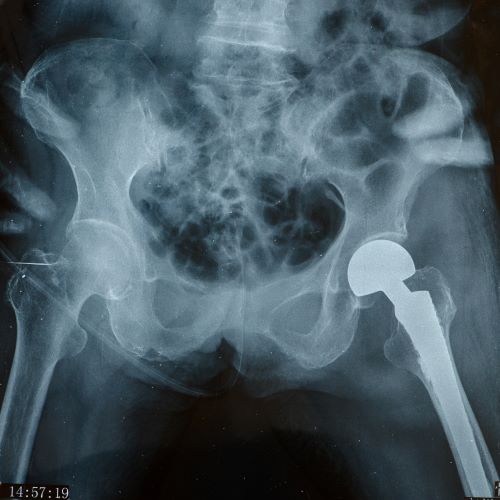

Эндопротезирование - это имплантация устройства, которое имитирует функцию здорового сустава. При этом, если с помощью протеза можно заменить, в принципе, любую часть тела (например, зубы, руки или ноги), то эндопротезы - это некий комплекс костей и искусственных компонентов, призванных поддерживать повреждённую часть человеческого организма. И используются они для замены тех частей сложного устройства - тела человека, которые могут быть восстановлены только при хирургическом вмешательстве.

Наиболее распространены операции по эндопротезированию плечевого, коленного и тазобедренного суставов.